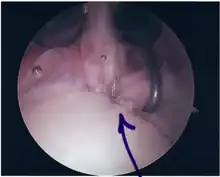

SLAP Tear

Arthroscopic SLAP Lesion (type 2) repair

Following inspection and determination of the extent of injury, the basic labrum repair is as follows.